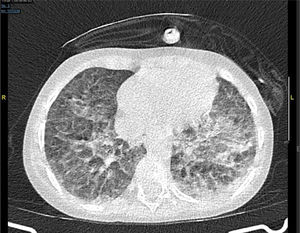

Al día siguiente, presenta progresión de la insuficiencia respiratoria a pesar de la recuperación de la aplasia medular y se realiza TAC torácica en la que se observan opacidades en vidrio deslustrado pseudonodulares y opacidades periféricas bilaterales (fig. 1).